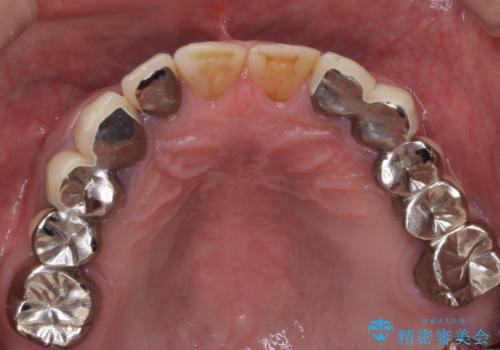

歯肉からの出血 適合の悪い銀歯をオールセラミックのブリッジにやり替え

- 右上奥歯の歯肉から出血があり異和感をおぼえ来院された患者様です。

以前の被せ物を除去し、仮歯に変えてすぐに異和感がとれました。

歯周治療を行い、歯肉が引き締まってから補綴治療しました。